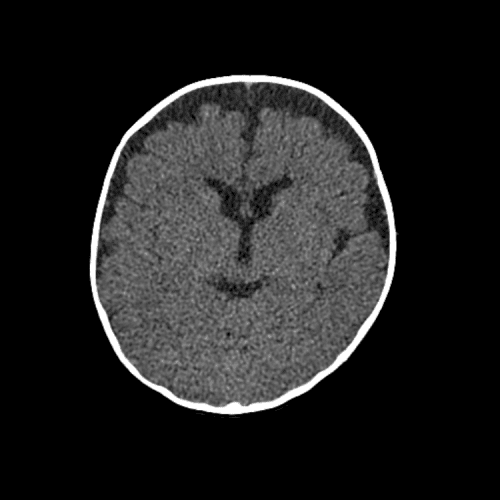

Watershed ischemia

Cardioembolic infarcts